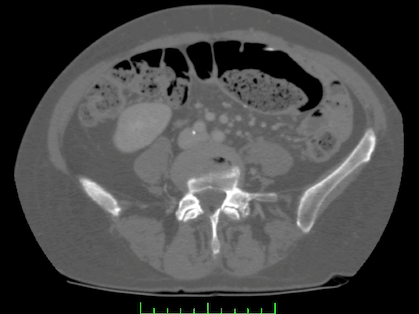

分割出CT腹部图像的肝脏区域。

实验中所涉及的信息源自3\text{D} Ricad\text{b}系统,并即是腹部CT图像数据。每个患者单独存储在一个独立的文件夹中。如3\text{D} Ricad 1.1版本包含20个不同的分割区域,则在对应的DICOM目录结构中有一个专门用于存储完整的人体切片序列的PATIENT DICOM目录以及一个专门用于存储各个解剖学部位分割结果的MASKS DICOM目录。其中,MASKS DICOM目录则包含了针对各个解剖学部位的不同分割结果区域,如肝脏以及肝脏肿瘤等解剖学区域等信息,如下图所示

PATIENT_DICOM利用软件展示效果如下:一个dcm文件包含129张切片。

MASKS_DICOM下的liver分割图效果如下: